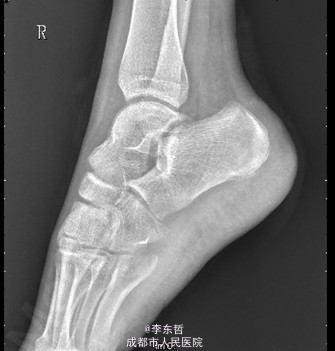

患者女,13岁4月,因“车祸致右足跟部皮肤撕脱伤清创缝合术后25天”入院。患者25天前因车祸导致右足疼痛流血伴功能障碍,右足跟部皮肤撕脱,遂到当地医院就诊,诊断为右足跟部皮肤严重剥脱伤,右跟骨骨折,右胫骨远端骨折。急诊下行“右足跟部皮肤严重剥脱伤清创缝合术”。术后给予止痛、消肿、预防感染等对症处理,目前右足外侧及跟部皮肤变暗,坏死。患者为进一步诊疗,故请我院远程会诊后转入我科继续治疗。患者病来精神、饮食可,大小便正常,体重未见明显改变。

查体:右足内踝、外踝及跟部皮肤变暗,部分缺血坏死。未见畸形,稍肿胀。触:右足趾皮温无明显降低,右足趾感觉未见明显异常。右足内踝、外踝及跟部皮肤局部压痛。动量:右踝关节活动受限,右踝关节活动诱发疼痛。右膝关节活动未见明显异常。 辅助检查:X线示:右跟骨骨折,右胫骨远端骨折。

初步诊断:1、右足跟部皮肤软组织撕脱伤清创缝合术后皮肤软组织大面积坏死伴感染;2、右跟骨骨折;3、右胫骨远端骨折;4、右足跖屈畸形。 处理:1、向患者及家属交待病情及注意事项。2、向上级医生汇报患者病情。3、完善相关术前等检查,择期行手术治疗。4、给予对症支持治疗。5、密切观察病情变化,根据病情及时处理。